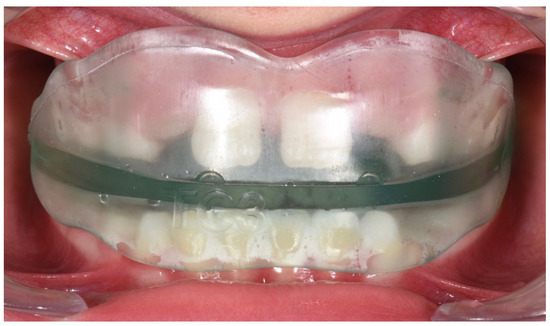

3.1. Clinical Case #1